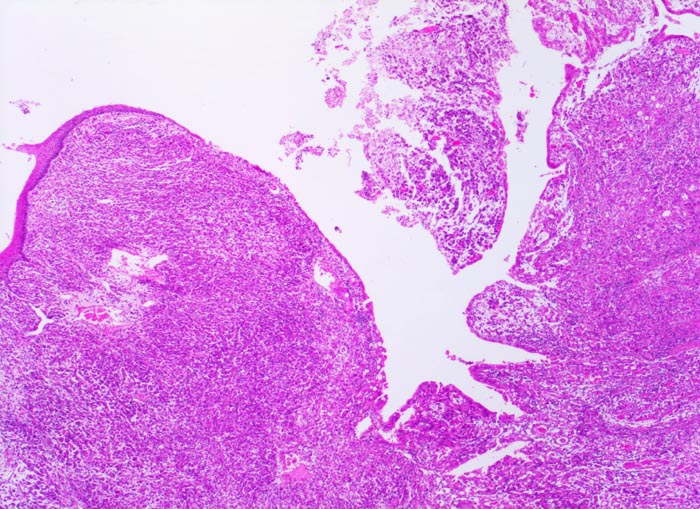

Magenkarzinom: Tumorinfiltration des Ösophagus

Oesophagogastrischer Uebergang

Das Karzinom breitet sich diffus in der Wand von Magen und Ösophagus aus. Die Ösophagusschleimhaut (links im Bild) und das Oberflächenepithel des Magens sind intakt.

Diffuse Verdickung und Versteifung der Magenwand im Sinne einer Linitis plastica bei intakter Schleimhautoberfläche. Aufhebung des Faltenreliefs.